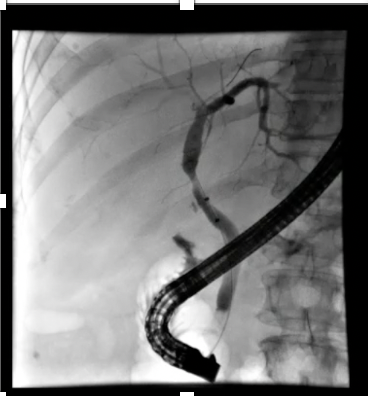

Aortoentertic fistula